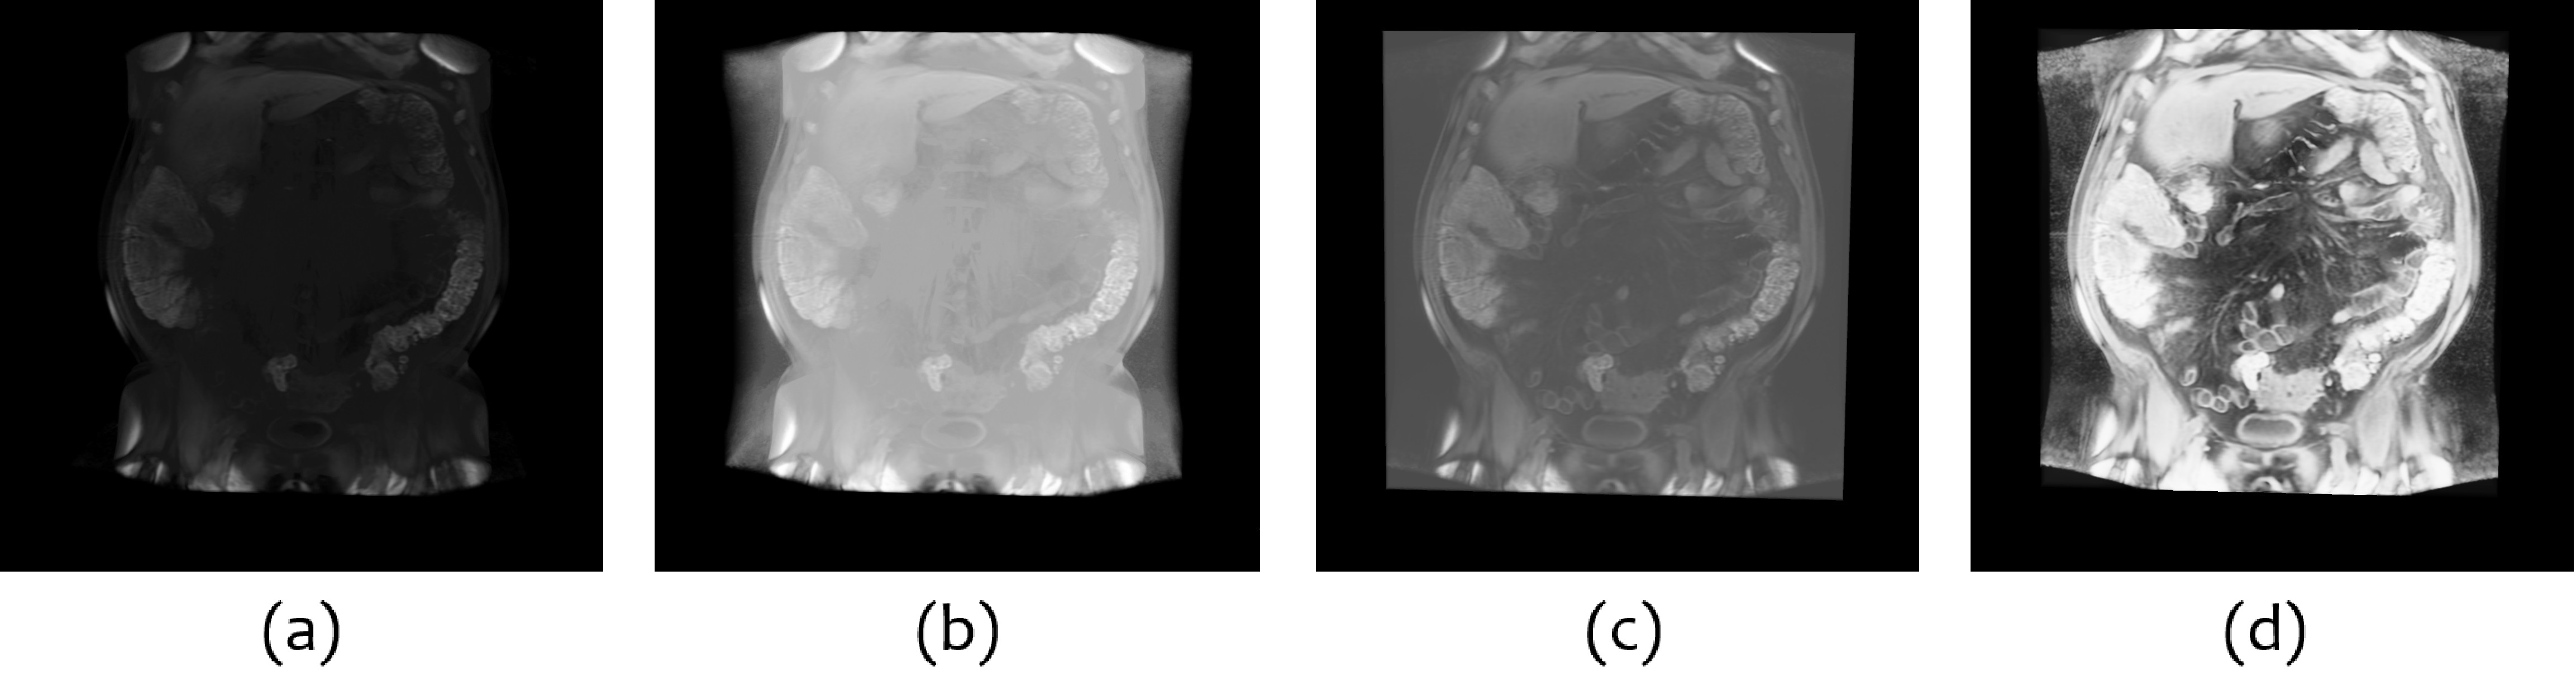

Therefore, we chose to integrate Lucknavalai and Schulze’s work [8] to perform real-time 3D Contrast Limited Adaptive Histogram Equalization (CLAHE) to enhance 3D medical image stacks. Fig. 4 compares the same volume data under the same setting only applies different contrast enhancement methods. Notice that for comparison, we only change one factor for each view. However, combined adjustments can be used to improve the quality further.

Refer to caption

Figure 4: Comparison of different contrast enhancement methods: (a) raw data volume, (b) only increasing the brightness, (c) only increasing the base value, and (d) using CLAHE